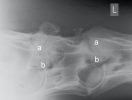

5. – 7. Halswirbel

Die Facettengelenke (a) sind vergrössert und nach unten unregelmässig zugebildet. Die Austrittslöcher (b) sind eingeengt.